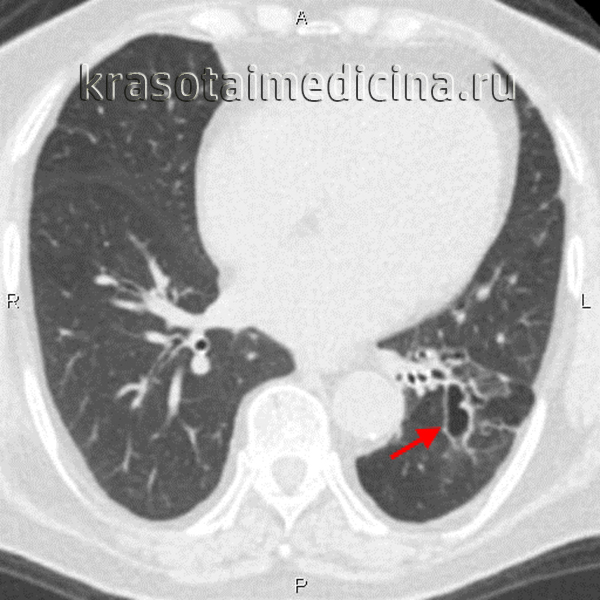

На прямой и боковой проекции рентгенограммы легких у пациентов с бронхоэктатической болезнью обнаруживаются деформация и ячеистость легочного рисунка, участки ателектазов, уменьшение в объеме пораженного сегмента или доли. Эндоскопическое исследование бронхов – бронхоскопия – позволяет выявить обильный, вязкий гнойный секрет, взять материал на цитологию и баканализ, установить источник кровотечения, а также провести санацию бронхиального дерева для подготовки к следующему диагностическому этапу – бронхографии.

Бронхография (контрастное рентгенологическое исследование бронхов) является самым достоверным диагностическим методом при бронхоэктатической болезни. Она позволяет уточнить степень распространенности бронхоэктазов, их локализацию, форму. Бронхография у взрослых пациентов проводится в под местной анестезией, у детей – под общим наркозом. С помощью введенного в бронхиальное дерево мягкого катетера происходит заполнение бронхов контрастным веществом с последующим рентгенологическим контролем и серией снимков. При бронхографии выявляется деформация, сближение бронхов, их цилиндрические, мешотчатые или веретенообразные расширения, отсутствие контрастирования ветвей бронхов, расположенных дистальнее бронхоэктазов. Для диагностики степени дыхательной недостаточности пациенту с бронхоэктатической болезнью проводят исследования дыхательной функции: спирометрию и пикфлоуметрию.